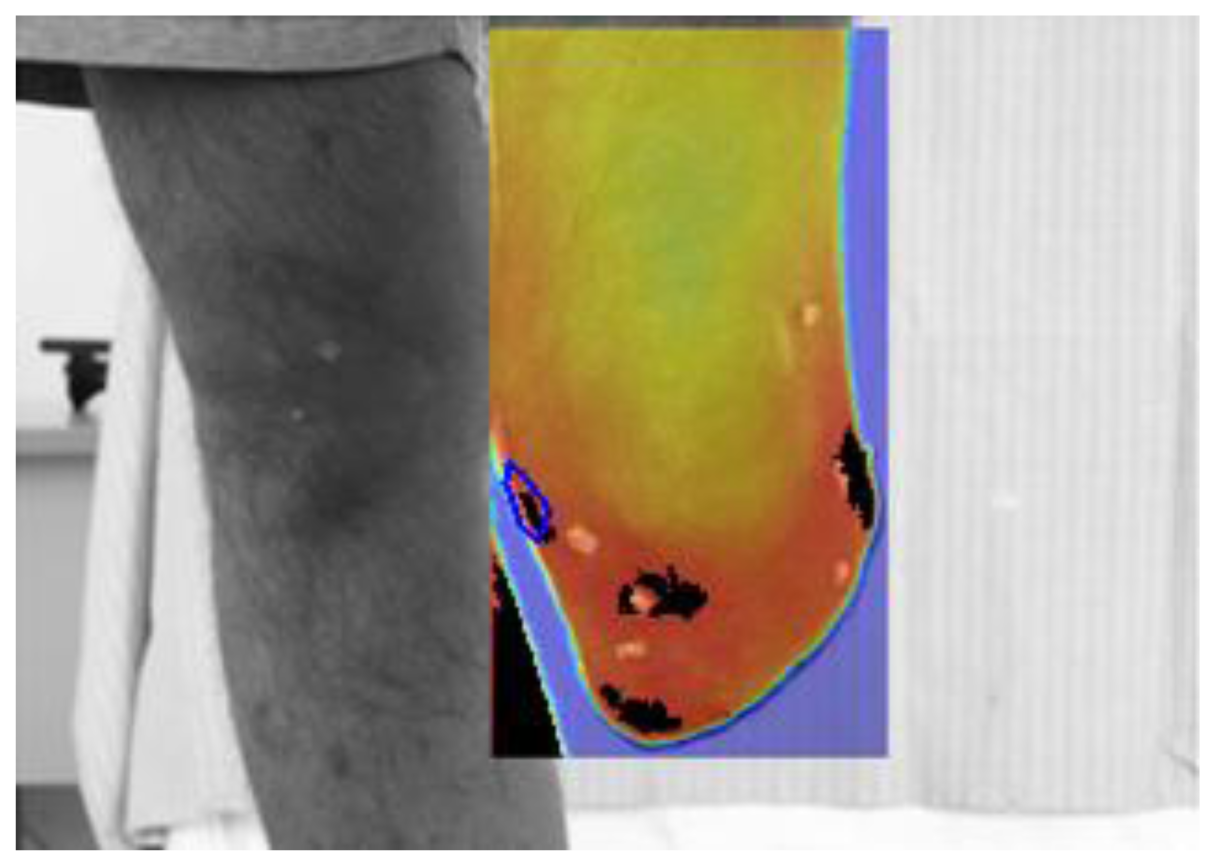

Prosthesis removal (also the liner is removed) and immediate thermal maps and visible image recording (Figure 5);

Regarding step 2, subjects are required to stand up on a spinning platform, with the stump vertical to the platform and aligned with its axis of rotation (Figure 5). Cameras stand on tripods and are not moved for collecting the different anatomical planes; instead the platform is rotated in steps of about 90° so that the whole subject rotates. While collecting basal images, the images collected after walking are used as reference to reposition the subject.

Regarding step 7, a dedicated software for infrared thermal maps analysis and integration with visible images and with the wearable sensors was developed in MATLAB (The Mathworks, Natick, MA, USA). The software implements a projective image-registration algorithm to superimpose “after-walking”, “basal” and visible images (Figure 6). The algorithm takes advantage of tiny ABS markers applied onto the subject's stump as starting guess for subsequent refinements. Then, isothermal images and differential thermal images are obtained for the whole image of specific regions of interest (ROI). The software also reads the Seeeduino data format and plots the time history of sensor recordings.